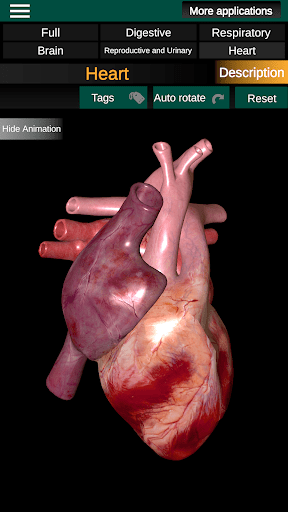

* Heart, which includes the atria, ventricles, aorta and an animation of this organ.

* Easy to access and navigate (zoom, 3D rotation).

* Hide or show information.

* Descriptions of each organ.